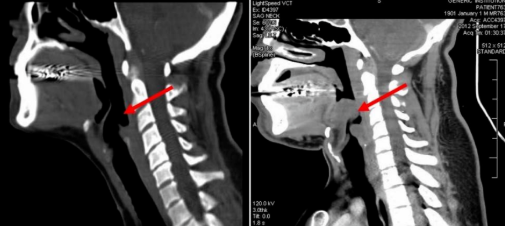

来到五官科时,我和一脸懵的同事说明情况,一致怀疑急性会厌炎。

会厌炎,就是会厌发炎。会厌位于舌根后方,形状类似于帽舌状。正常情况下,我们在进食时,食物经过咀嚼形成球状,这个时候会厌会自动关闭,以防止食物进入我们的肺部。

如果会厌发炎肿胀,就可能堵塞呼吸道,这个时候自然就会呼吸困难。

由于急性会厌炎病情进展十分迅速,所以如果发病后未及时获得诊断治疗,可在短时间内窒息,死亡率十分高。